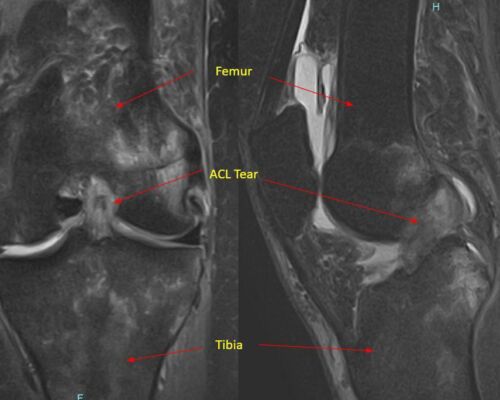

Dr. Pancio studied my daughters MRI before he came in and talked to us. He examined her knee and told us that her exam confirmed what he had found on the MRI which was missed by the radiologist. He prescribed the appropriate physical therapy and my daughter is on her way to making a full recovery without surgery! If she would have needed surgery, we have full confidence that Dr. Pancio would be great! He is very observant and knowledgeable. He explained everything that is going on with her knee also why and when it would hurt in different situations.